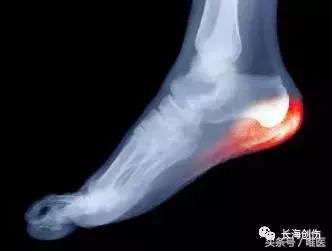

◎ X-光检查可看到足跟骨刺(heel spurs),但有15%的人有长骨刺但没有症状。